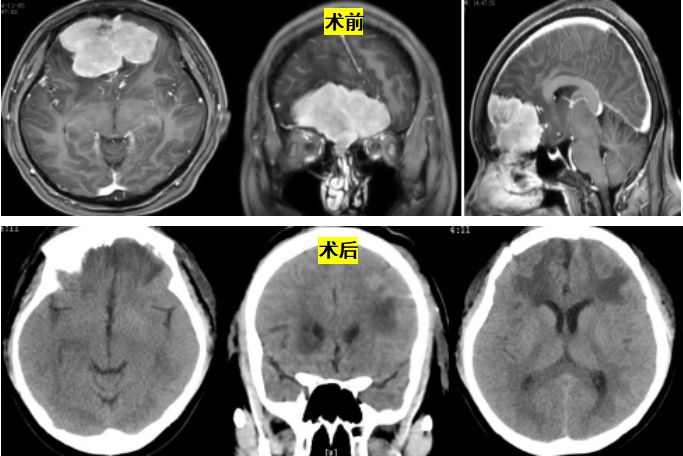

患者是一位以癫痫起病的年轻病人,经系统检查发现患者肿瘤位于额部前颅底区域,脑膜瘤可能性大,肿瘤大小约7.2x3.9x5.1cm,病变周围脑实质受压并大片水肿,侧脑室及中线结构受压,患者治疗意愿强烈。

经过神经外科缪星宇主任团队系统化的专业评估科室手术讨论,患者手术指征明确,术前经过严格的手术路径设计,拟在术中使用3D外视数字手术显微镜。此系统结合了显微镜与神经内镜功能,使得传统手术方式发生了根本性的变化。与传统的基于目镜的显微镜相比,该系统提供了更清晰的画面、更优越的景深、更广阔的视野,基于优秀的照明技术及背光照明3D荧光模式应用,让神经外科医生能更精确地观察术野组织及血管,进一步提高手术精度;另外神经外科医生在进行手术时可以保持一种符合人体工学的舒适姿势进行手术,助力术者以更便捷舒适的方式高效完成显微外科手术,显著提升团队协作和教学效果。在3D外视数字手术显微镜的帮助下,手术团队精准切除肿瘤,达到对神经功能的最大保护,患者顺利康复出院;术后病理证实为脑膜瘤(WHO I级)。